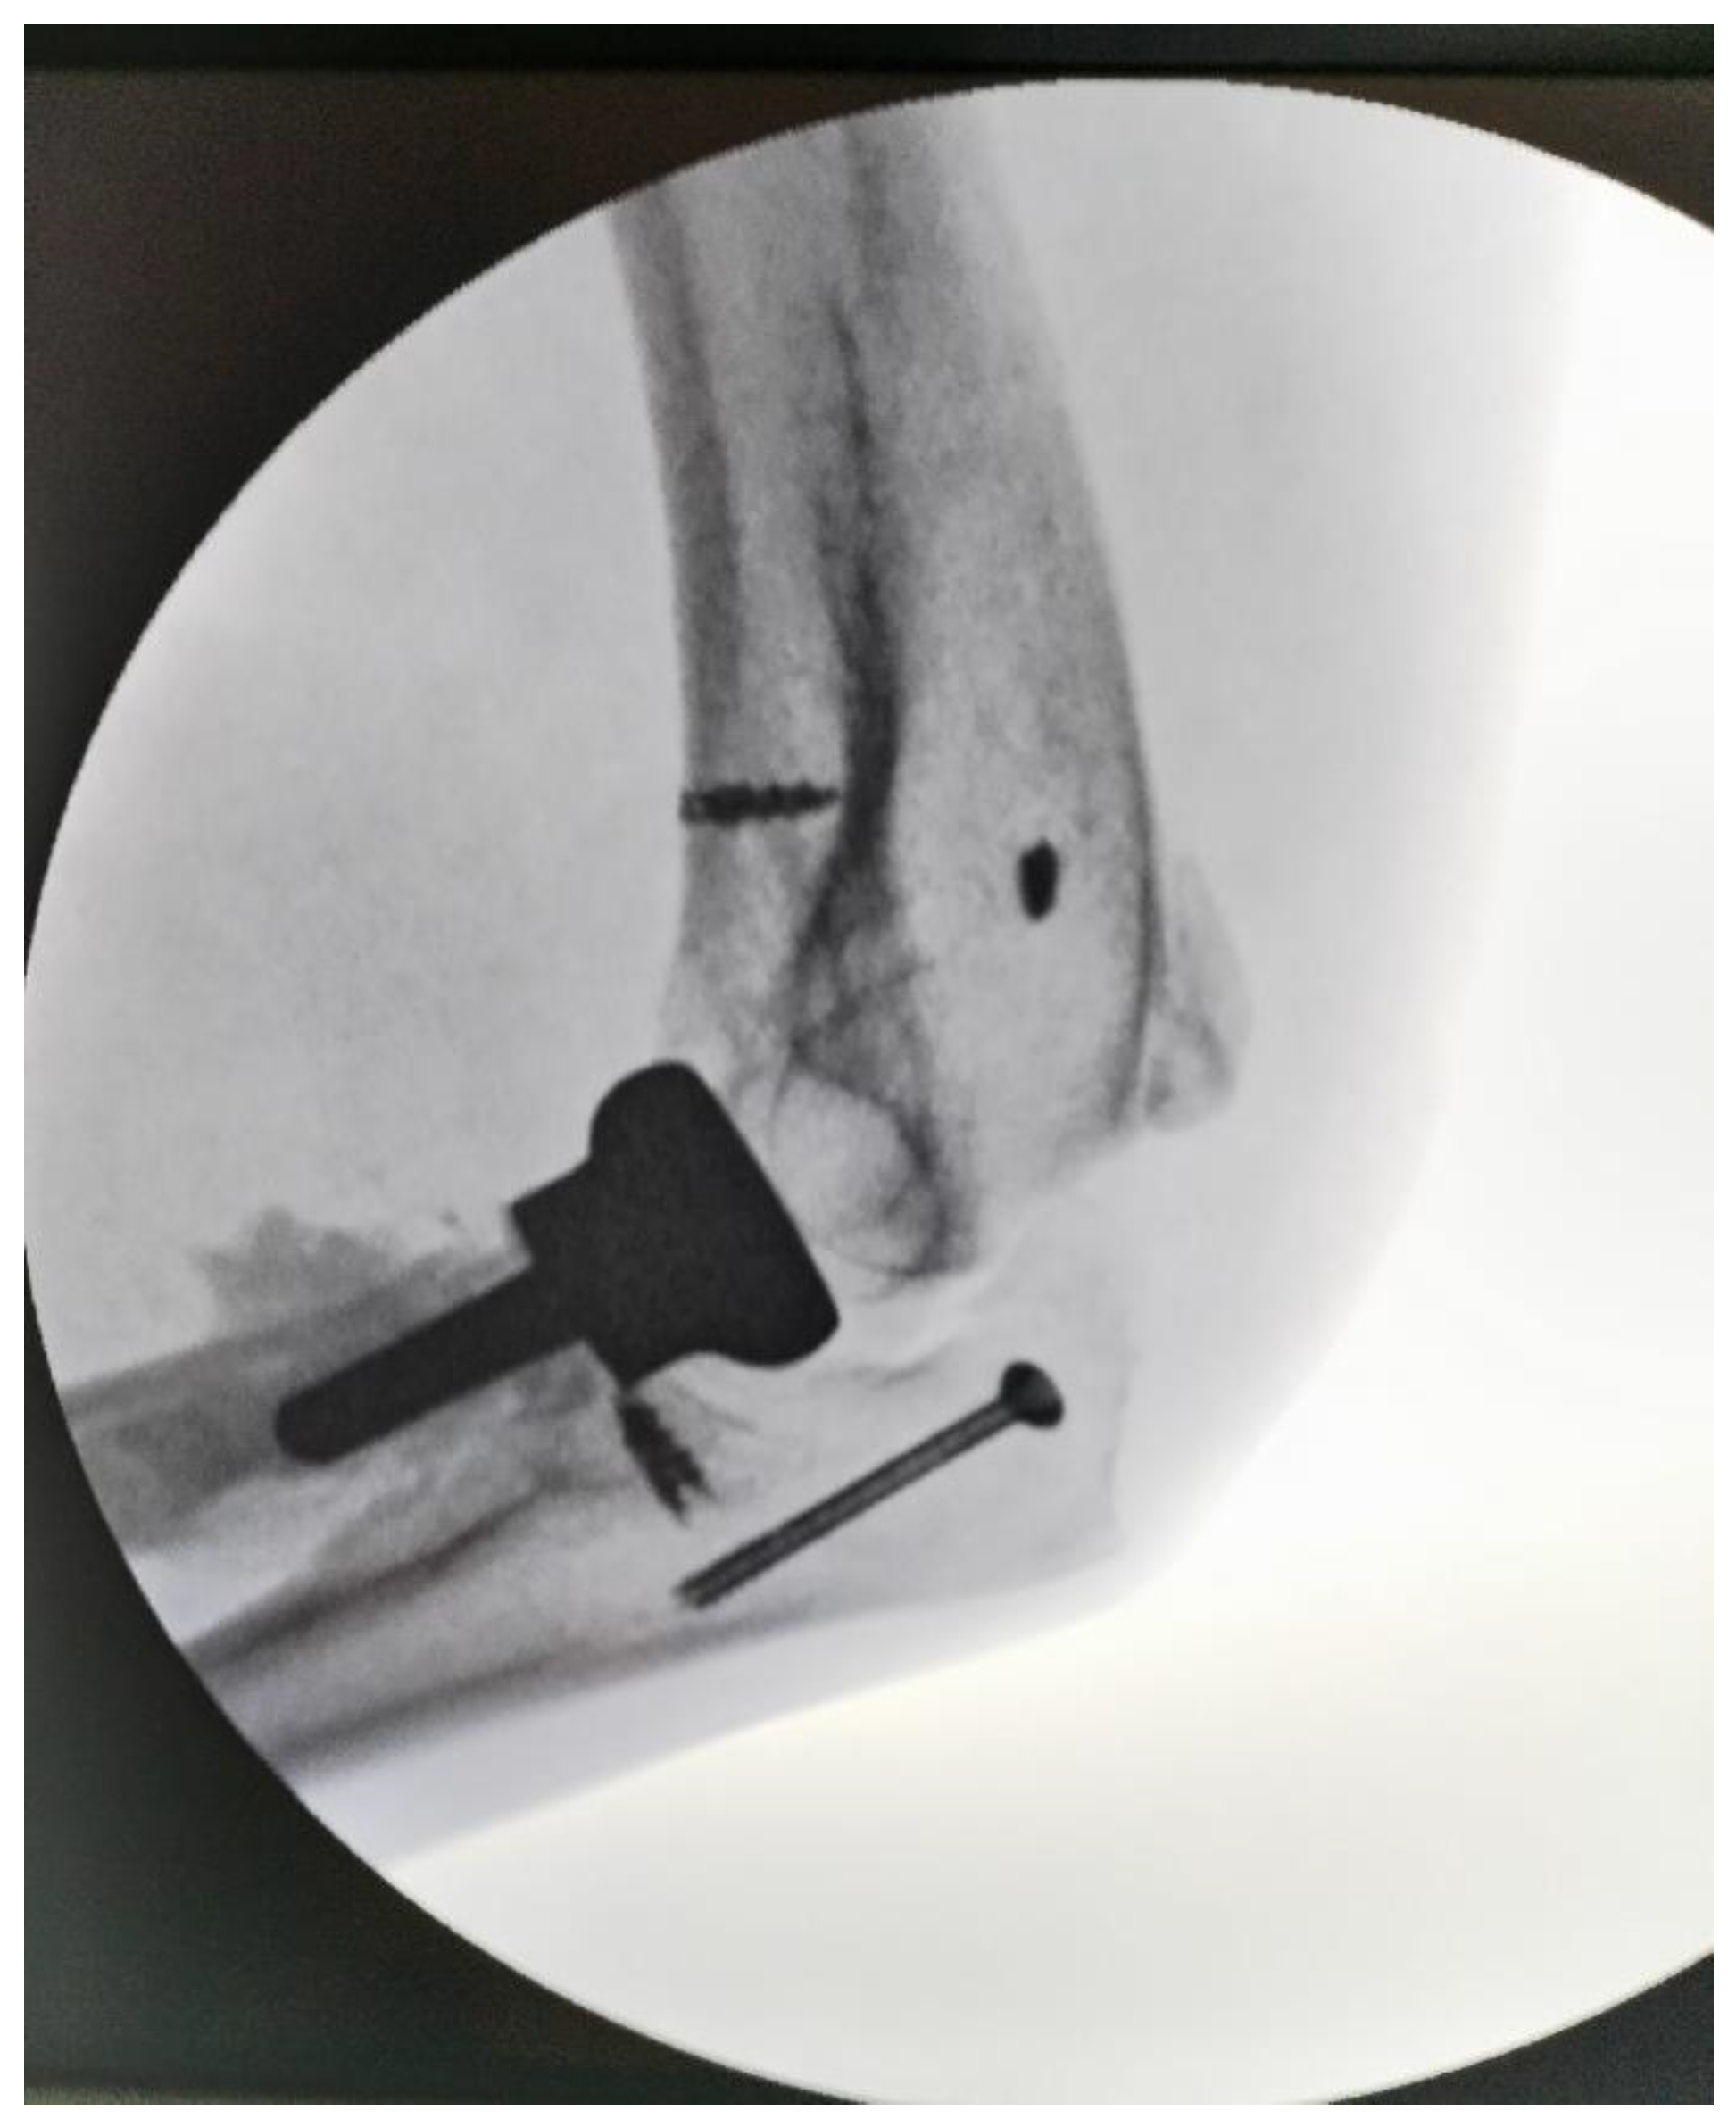

The common extensors were attached with anchors and ulnar nerve anterior transposition was made at the end of procedure. Soft tissue was sutured with elbow at 90 degrees and with radius in pronation to use as stabilizer prosthetical head. Then postoperative X-ray was taken to evaluate the elbow joint alignment (Figure 4). The wound was closed in a standard manner over a suction drain to prevent the accumulation of a subcutaneous hematoma.

At two weeks the sutures were removed. The following follow-ups took place at 6 weeks, then three months after surgery, and the last at 18 months later, on which occasion MEPI score was evaluated when patient obtained 95 (Table 2). At 4-6 weeks after surgery, gradually, the passive motion was replaced by active motion. No wound infection, or ulnar nerve deficit were noted. Follow-up imaging at 18 months postoperatively included plain radiographs, which confirmed maintained reduction, proper positioning of the radial head prosthesis, and no recurrence of heterotopic ossification. (Figure 5).

Figure 5. a) Lateral and b) anterior view of elbow at 18 months after surgery.